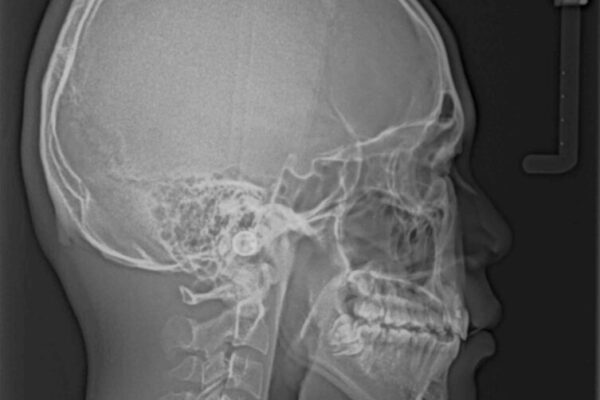

治療前

• 膨らんだ口元 ワイヤー装置での抜歯矯正 治療前画像